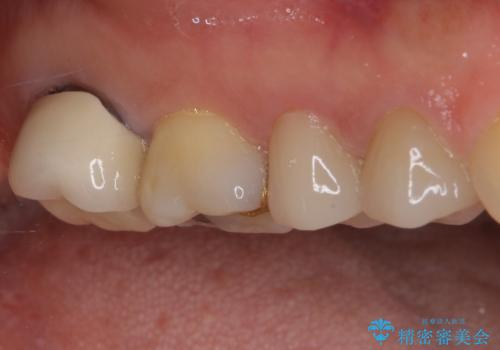

ゴールドインレーは銀歯のインレーやセラミックインレーと比べ、「技工操作の精度が高く、適合が著しく良い」というメリットがあります。特に上の奥歯は歯科医師の操作が行いにくいため、「適合の良さ」は再治療のリスクを防ぐ上でとても重要な要素となります。

上の奥歯は金属色が見えることもないため、審美的な問題は全くありません。

咬合力が原因と思われるむし歯治療では、ゴールドインレーが第一選択になるといっても良いかもしれません。